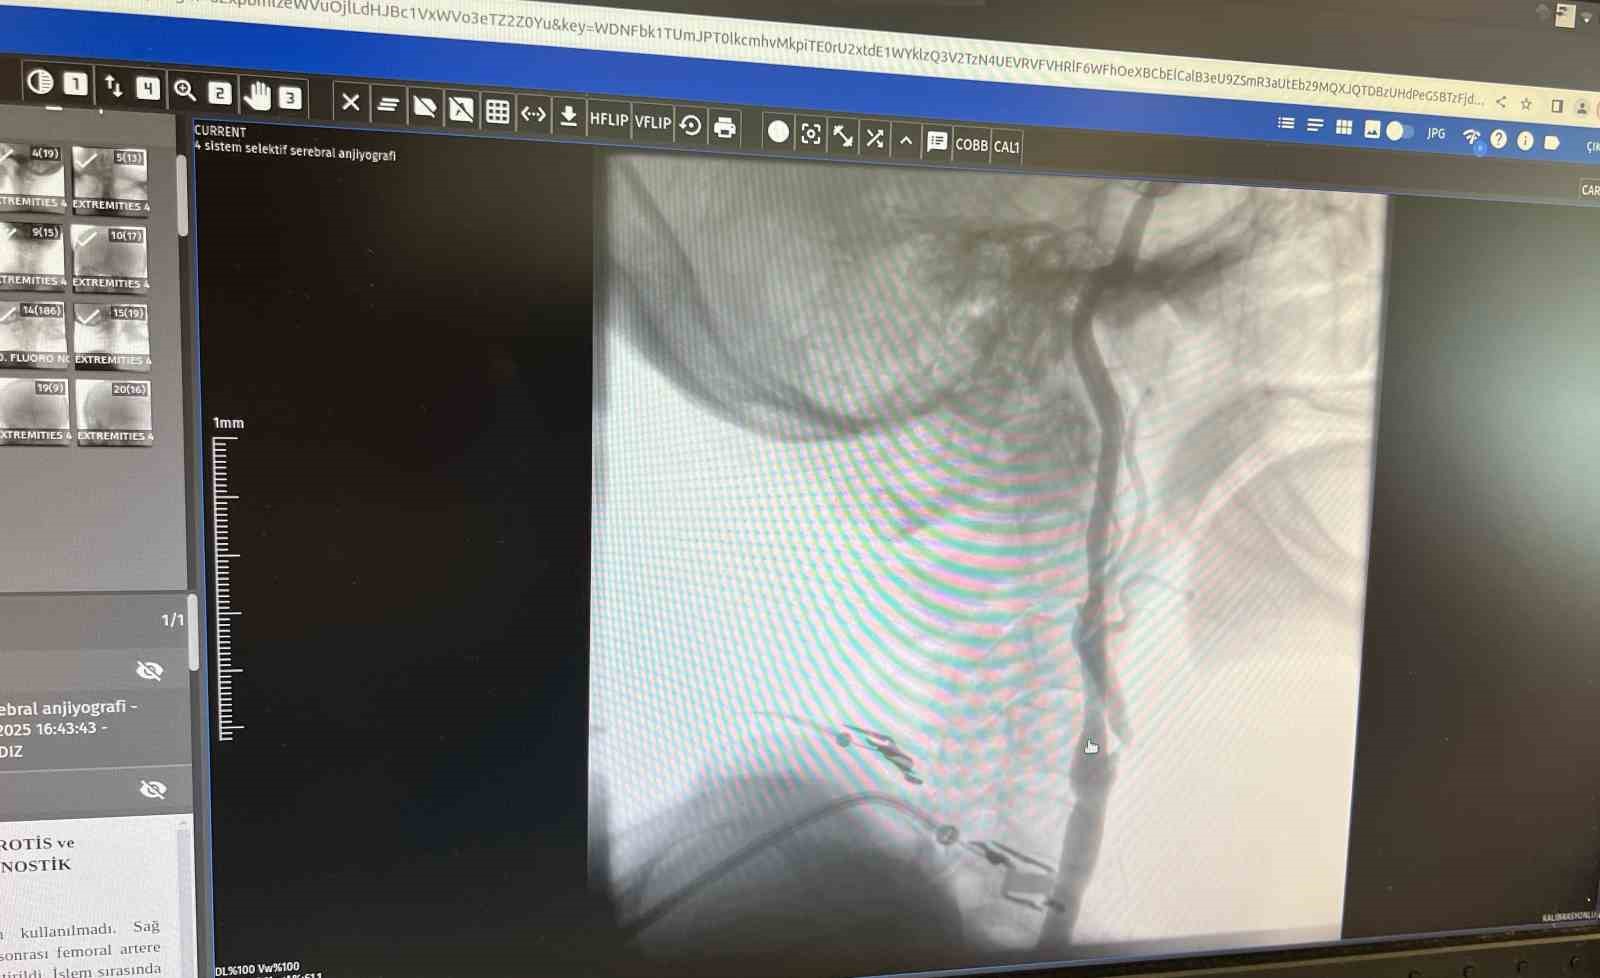

Manisa Şehir Hastanesi’nde girişimsel nöroloji ve girişimsel kardiyoloji uzmanlarının iş birliğiyle, beyni besleyen en büyük damarlar olan karotis (şah) damarlarındaki tıkanıklıklara karşı modern tedavi yöntemleri başarıyla uygulanıyor. Uzmanlar, bu damarlarda gelişen ciddi darlıkların inme (felç) riskini önemli ölçüde artırdığını belirtiyor. Bu nedenle, felç riskini azaltmak amacıyla hastalara stentleme işlemi uygulanıyor.

Girişimsel Nöroloji Uzmanı Doç. Dr. Ezgi Sezer Eryıldız, "Beynimizi besleyen en büyük damarlar karotis damarları yani şah damarlarıdır. Eğer bu damarlarda ciddi bir darlık olursa inme yani felç geçirme riski belirgin şekilde artmaktadır ve bu riski azaltmak için stentleme işlemi uygulanmaktadır. Rutin olarak hastalarımız bu açıdan değerlendiriliyor ve bu işlemi uyguluyoruz" dedi.

"Boyun damarlarını açma işlemi iki şekilde yapılabilir. Bir karotis endarterektomi dediğimiz ameliyatla bir diğer yöntem ise perkutan girişim dediğimiz stent yöntemiyle açılabilir. Biz kliniğimizde nöroloji ve kardiyoloji olarak bir konsey yapıyoruz. Damarı ciddi tıkalı olan ve buna bağlı felç geçirmiş hastalarda bu konseyde hastaya işlem yapıp yapmama kararı veriyoruz. Verdiğimiz karar çerçevesinde eğer hastaya işlem kararı vermişsek femoral arter dediğimiz kasık arterinden bir şitle 6 ya da 7 F çapında bir şitle ince bir boruyla bu damara giriş yapıyoruz ve boyun damarlarına ulaşıyoruz. Özellikle teller, filtreler ve stentlerle bu damarları açıp hastanın tedavisini gerçekleştiriyoruz. İşlem ameliyatsız olduğu için hastamız ertesi gün rahat bir şekilde problem olmazsa işlemde taburcu olabiliyor bu işlemden sonra. Bu işlemin yapılması için özellikle anjiografinin olduğu girişimsel nöroloji uzmanının ve girişimsel kardiyoloji uzmanının olduğu ve bu konuda yeterli vaka tecrübesine ve deneyime sahip uzmanların olduğu merkezler gerekir. Bunu yapabilmek için belli bir vaka sayısına ulaşmak ve bu konuda tecrübeli olmak gerekiyor. Biz de Manisa Şehir Hastanesi’ndeki girişimsel kardiyoloji ve nöroloji uzmanları olarak bu işlemi kliniğimizde efektif bir şekilde gerçekleştiriyoruz."